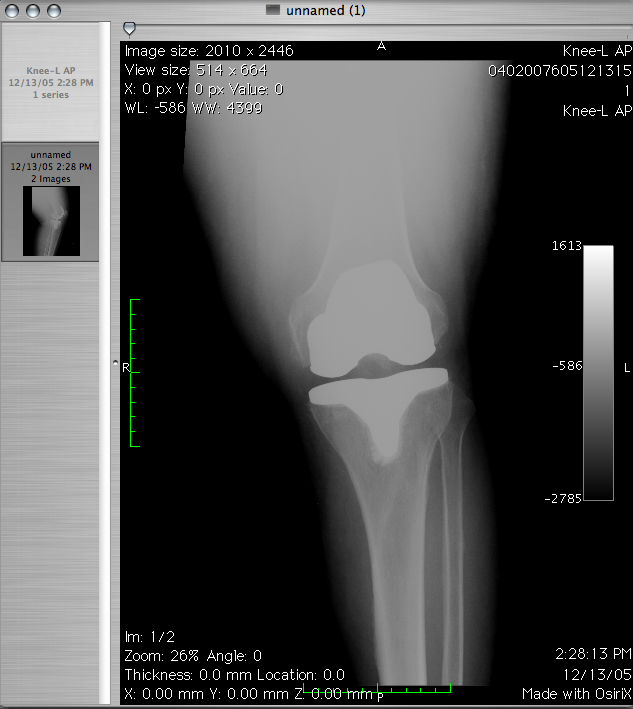

Obecnie bardzo wiele spotyka nas różnych wypadków. Bardzo intensywny tryb życia czy aktywne uprawianie sportu …